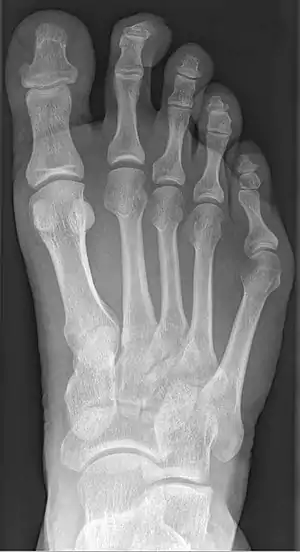

Radiograph showing a tailor's bunion

Tailor's bunion is easily diagnosed because the protrusion is visually apparent. X-rays may be ordered to help the surgeon find out the severity of the deformity.

Types of Tailor Bunions [3]

Type 1: the head of the 5th metatarsal is thickened and enlarged

Type 2:  a 5th metatarsal with an increased lateral curve and a normal fourth and fifth intermetatarsal angle

Type 3:  has the greatest lateral angular disposition of the 5th metatarsal compared to the 4th metatarsal, this phenomenon increases the 4th and 5th inter-metatarsal angles. This is generally, the most symptomatic TB is type 3.

Type 4: a combination of at least 2 types of bunionettes (TB)